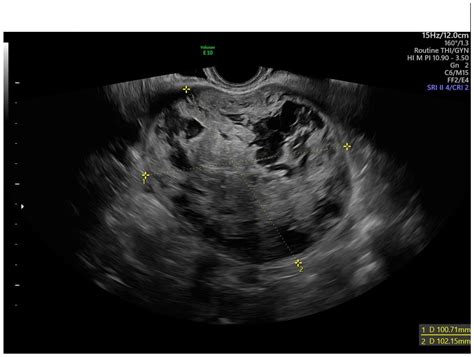

Diagnosing uterine myoma degeneration involves a combination of medical history, physical examination, and imaging tests. The diagnostic process typically includes:

• Imaging Tests: Ultrasound, MRI, or CT scans to visualize the fibroids and assess the extent of degeneration.